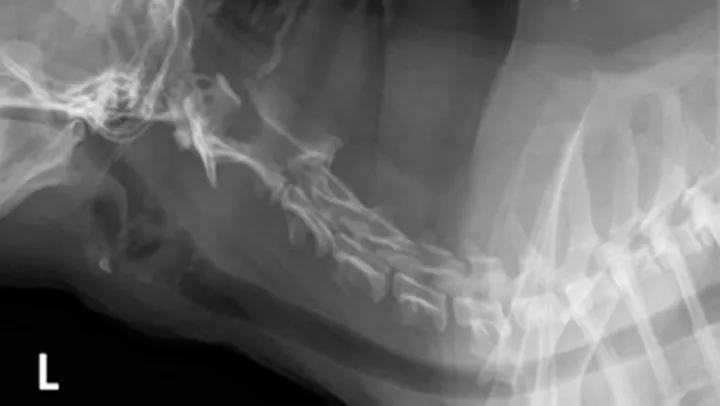

In this case, cervical radiographs (Figure 2) showed scoliosis (which could not be manually corrected under sedation) but no other abnormalities. MRI of the cervical spine and brain (Figure 3) was performed because of the diagnostic considerations, clinical severity, and progressive nature of the signs.